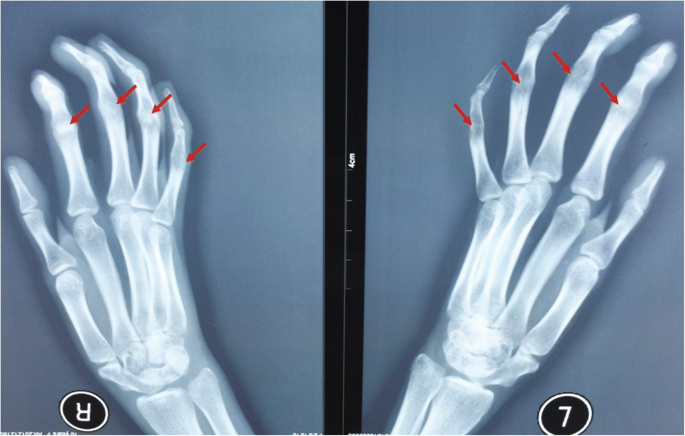

The following hand findings are called:

Symphalangism (failure of IP joint to differentiate)

AD - OR - Apert's;Poland's